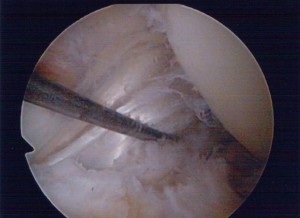

The MCL is usually injured by a contact blow to the outer side of the knee. MCL injuries typically heal without surgery but sometimes the knee needs to be fitted with a brace. ACL ruptures will not heal and in many cases an ACL reconstruction is required. We perform arthroscopic (“key-hole”) ACL reconstruction usually using a hamstring graft. We also perform revision (re-do) ACL reconstruction in those patients who re injure and tear their ACL reconstructions or who have been referred to us with poorly functioning ACL grafts.